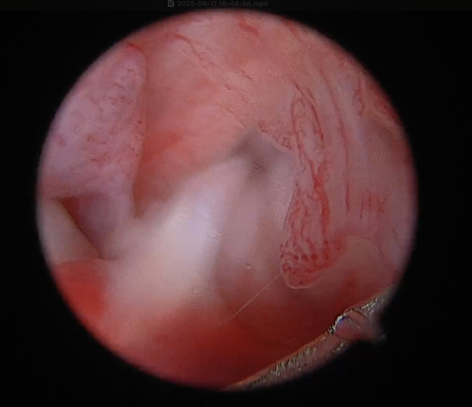

2) 관절경 확인

- 완전히 끊어진 게 아니라 일부만 찢어진 경우에는 drawer test나 tibial compression test가 각도에 따라 약하게 나오거나, 어떤 때는 명확하지 않을 수 있습니다

관절경은 관절 안을 직접 보니까, “진짜로 어느 부위가 얼마나 남아 있는지/어느 밴드가 손상인지”를 눈으로 확인할 수 있어 진단을 더 확실하게 만들어 줍니다.

- CCLD에서 meniscus가 같이 찢어지는 경우가 흔하고, 이게 있으면 통증·파행이 더 심해지거나, 수술 후에도 절뚝거림이 남는 원인이 될 수 있습니다.

특히 meniscus는 관절 밖에서 촉진이나 X-ray로는 “직접” 확인이 어렵고, 클릭 소리가 없거나 증상이 애매하면 놓치기 쉬운데, 관절경으로는 찢어진 부위/불안정한 조각을 직접 확인하고 필요한 처치를 같이 할 수 있습니다.

.png)

전방 십자인대 손상 확인 된 모습

후방 십자인대 부분 손상 및 염증성 변화 확인

손상되지 않은 반월판 확인 된 모습